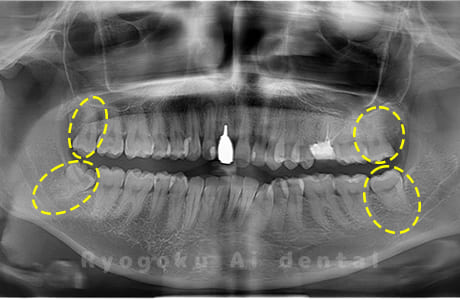

Case04

- 上顎の親知らず、下顎の水平埋伏の親知らず

- 上顎の親知らず、下顎の水平埋伏の親知らずを抜歯したケースです。

<リスク・副作用>

手術後は痛み、腫れ、痺れなどの副作用が生じる場合があります。